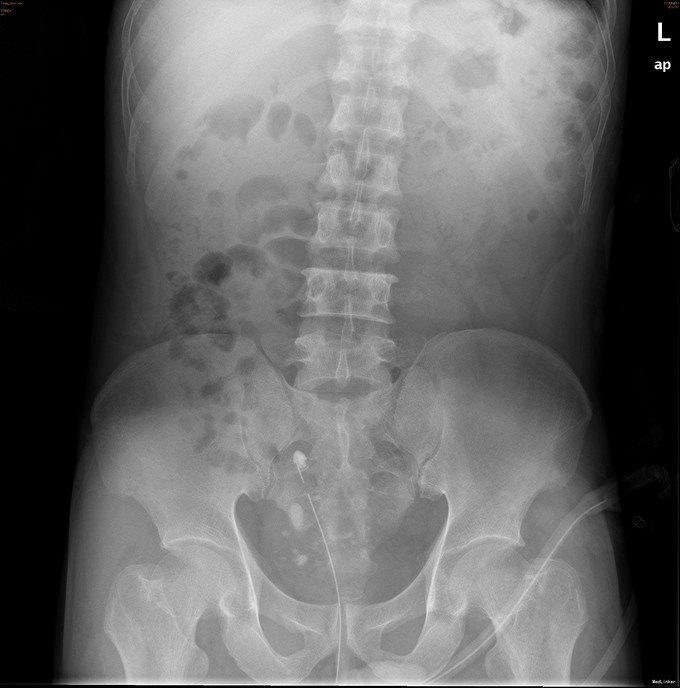

腹部平软,下腹正中可见一长约4cm纵行手术疤痕,无压痛,双肾区无叩痛,双输尿管走行区无压痛,膀胱区不胀,无压痛,留置导尿管引流尿液通畅,尿色淡红清亮。外生殖器发育正常,未见明显畸形,双侧阴囊色泽大小正常,双侧睾丸可扪及,大小质地正常,无压痛。前列腺指诊:前列腺Ⅱ°增生,质地韧,表面光滑,中央沟变浅,未及明显结节,无压痛,退指未见血迹。 既往于30年前曾行“膀胱切开取石术”。 辅助检查:2015-02-03当地市人民医院 B超示:“双肾重度积液,膀胱结石(大小约3.8*2.1cm)”。 泌尿系彩超:双肾重度积液。左肾结石。双侧输尿管扩张,右输尿管下段可疑结石。膀胱结石。局部膀胱壁增厚,膀胱憩室形成。前列腺超声检查未见异常。 腹部平片:1、结合病史,考虑膀胱多发结石。 2、导尿管留置术后改变。

膀胱结石;右输尿管结石;前列腺增生;肾功能不全;双肾积液。 经尿道膀胱钬激光及弹道碎石取石术 经尿道输尿管镜激光碎石术+经尿道膀胱颈电切术